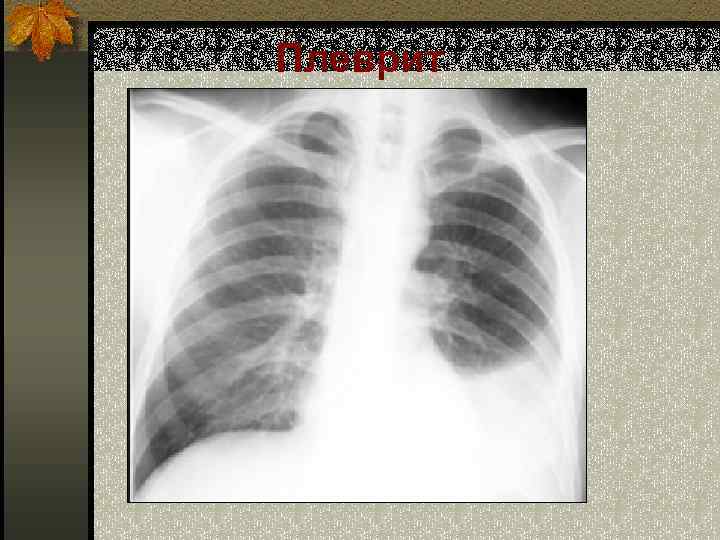

Плеврит